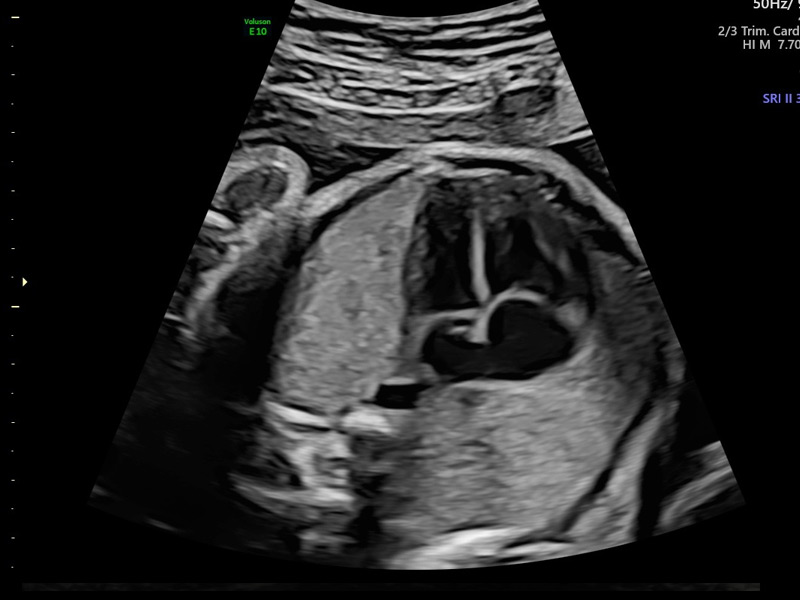

Ecografía morfológico – scan del 2° trimestre

Conocida como ecografía morfológica fetal, se realiza entre las semanas 20 y 24 del embarazo. Esta prueba analiza la cabeza, el tórax, el corazón, el abdomen, el diafragma, la columna, la cara, las extremidades, los genitales externos, el líquido amniótico, el cordón umbilical y la placenta. Su objetivo es diagnosticar alteraciones en la morfología fetal.